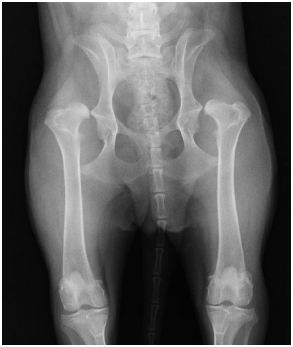

Canino com queixa clínica de claudicação e intolerância ao exercício foi submetido a um exame de imagem. Evidenciou-se, pelo exame, que o ângulo de Norberg foi menor que 90° com visível achatamento acetabular cranial, sem sinais de osteoartrose.

Qual o diagnóstico desse animal?